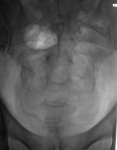

Травма (ДТП) в мае месяце. На контроль пришел на костылях.

Компрессионный перелом L4. Клин Урбана сдавливает элементы конского хвоста. Синдром конского хвоста(?). Необходима срочная декомпрессия.

пишут не рентгенологи, а клиницисты. О сдавливании элементов хвоста, кроме клиницистов, могут еще судить магниторадиологи. Наш (общий на всех) термин - стеноз позвоночного канала. Еще надо не лениться и указать степень компрессии компрессии тела - легкая (20-25%), умеренная (25-40%), выраженная (больше 40%). А также замерить расстояние между основаниями дуг позвонков в прямой проекции - у L4 оно явно шире, и тогда в дополнение к перелому тела добавится перелом дуги и термин "нестабильный". Для полной красоты следует указывать угол кифотической деформации; критическими значениями являются:  для шейного отдела - 11º,  для грудного – 40º,  для поясничного - 25º

а здесь еще и переломовывих L4. а перелом еще и оскольчатый. с такой картиной можно утверждать что инвалидизация пациенту светит.А в S4 я перелома не вижу.